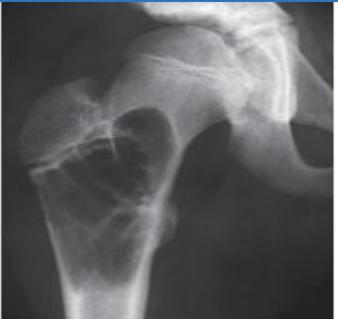

| Compartment Syndrome | Increased pressure within a closed fascial compartment, leading to reduced tissue perfusion, hypoxia, and irreversible muscle and nerve damage. Causes: Fractures (especially tibia/forearm), severe soft tissue trauma, arterial injury, burns, tight casts/dressings, post-ischemic reperfusion swelling, IV fluid extravasation, and bleeding disorders (e.g., hemophilia). High-Risk Notes: Pain may be absent in altered consciousness, children (monitor analgesia response), polytrauma, sedated/epidural cases, or concomitant nerve damage. Open fractures do not always decompress pressure. Gross/Clinical: -tense, shiny leg swelling with blisters in compartment syndrome.Imaging: - Intraoperative fasciotomy | History/Symptoms: Pain out of proportion to the injury (e.g., a “bursting” sensation), which is not relieved by analgesia. Clinical Features (The 5 P’s): - Pain with passive stretch (early, key sign; e.g., ankle dorsiflexion for leg, wrist for forearm). - Paresthesia (early). - Palpable tense swelling (shiny skin, blisters: clear=mild, serosanguinous=severe, bloody=worst; dusky/pallor skin). - Pallor, Paralysis, Pulselessness (late, ominous signs; pulses often palpable until late). Investigations: Primarily a clinical diagnosis (high suspicion key). Compartment pressure measurement can confirm: absolute pressure >30 mmHg or Delta Pressure (Diastolic BP - Compartment P) ≤ 25 mmHg. | Initial: ABCs, supplemental oxygen. Remove all circumferential dressings, casts (bivalve to skin), and splints. Elevate the limb to heart level (not above; higher reduces inflow). Correct any hypotension. Surgical: Urgent Fasciotomy if no response within 1h or confirmed pressure (prophylactic in high-risk like major osteotomy). Release all compartments/skin with long incisions; debride necrotic muscle via 4C’s (early: pink/red, soft, contracts/bleeds on pinch; late: dark, firm, no response); preserve neurovascular. Wound open (bulky dressing/splint, VAC, or boot-lace gradual closure); repeated inspections x48h; coverage in 3-5 days (skin graft usual; flap if nerves/vessels/bone exposed). | Cellulitis, Deep Vein Thrombosis (DVT), Arterial occlusion, Severe soft tissue injury without compartment syndrome; equivocal cases in polytrauma. | Complications: Volkmann’s ischemic contracture (permanent deformity, weakness, sensory loss, chronic pain). Contraindications (Fasciotomy): Confirmed >48h (irreversible damage, high infection risk from dead tissue); crush injuries with already necrotic muscle. |

| Open Fracture | A fracture with a breach in the overlying skin and soft tissues, creating communication with the external environment. All open fractures are considered contaminated (even small punctures; aka compound fracture). Causes: Can result from high-energy trauma (RTAs, falls, firearms; signs: degloving, crush syndrome, bone loss, segmental) or low-energy trauma. Contamination risk higher with farm/soil injuries, bites, delayed presentation (>12h), fecal/oral/soil/water exposure. Mechanism: Low/high velocity missiles (cavitation >300 m/s); in-out (cleaner) vs. out-in (dirtier). Gross/Clinical: ![]() | History: Mechanism of injury (energy, time, place, type/impact method), consciousness, wound size/bleeding amount, other injuries (often missed), tetanus status. Assessment: ATLS protocol (ABCDE) first (treat patient, not fracture; exclude shock/brain injury, monitor vitals; viscera exam: ribs=lungs/liver/spleen, pelvis=bladder/urethra). Examine wound (look/feel/move carefully post-splint), check distal neurovascular status, compartment syndrome. Photograph/remove gross contamination; cover with saline dressing. Classification (Gustilo-Anderson): - Type I: <1 cm wound, clean, minimal soft tissue. - Type II: >1 cm wound, moderate soft tissue (no stripping). - Type IIIA: Extensive soft tissue damage, but adequate bone coverage. - Type IIIB: Extensive soft tissue loss with periosteal stripping; bone exposed, requires flap coverage. - Type IIIC: Any open fracture with an arterial injury requiring repair. | Initial (ER): ATLS first. Cover wound with sterile saline-soaked dressing, splint limb, IV fluids (request blood if needed); traction if no distal pulse/deformity. Prophylaxis: Tetanus prophylaxis/serum and broad-spectrum IV antibiotics immediately (culture tissue/blood); clean major contamination. Surgical: Urgent debridement/irrigation within 6-12h (“Dilution is the solution to pollution”; pulse-irrigate 3-6-9L saline; excise non-viable tissue/foreign material, trim skin edges, remove dead muscle/detached bone, preserve N/V). Stabilization: external fixator (preferred severe; replace with cast post-infection); internal if clean/minimal. Wound closure delayed (primary if small/clean; secondary if contaminated/large). Early soft tissue cover. | The diagnosis is typically obvious. Key: Classify severity; identify associated injuries like compartment syndrome, vascular damage, or high-energy signs (e.g., crush). Differentials for contamination: Primary (field debris) vs. secondary (post-fixation if poor debridement). | Complications: Infection (cellulitis, osteomyelitis, chronic with sequestra/drainage, gas gangrene), tetanus; higher with delay/exposure/bites. - embolisms fat, thrombi others.. Case Insight: Unconscious patient (e.g., open tibia post-RTA): ABCDE/cervical collar, distal pulses/traction, admit for debridement; ankle fall: Splint post-ABC, assess neurovascular. |